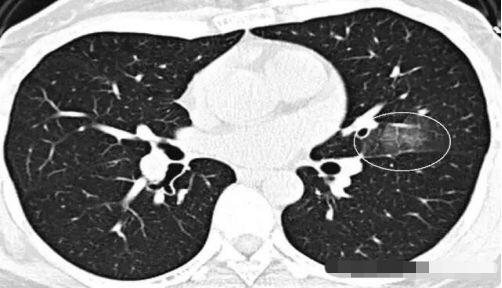

2. 那么,王大夫,这个磨玻璃影那么多,是不是也是肺癌呢?

呵呵,这个也不是啦,这个叫马赛克灌注,是肺内通气灌注不一致的表现,主要是小支气管炎症,导致肺内局部积气,像马赛克拼图一样。不是肺癌,当然不用担心啦。